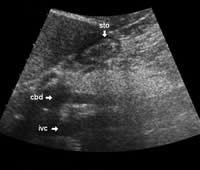

The following study describes anatomical landmarks in the ordinary pancreas of a thin patient:

Transverse planes in caudal direction: